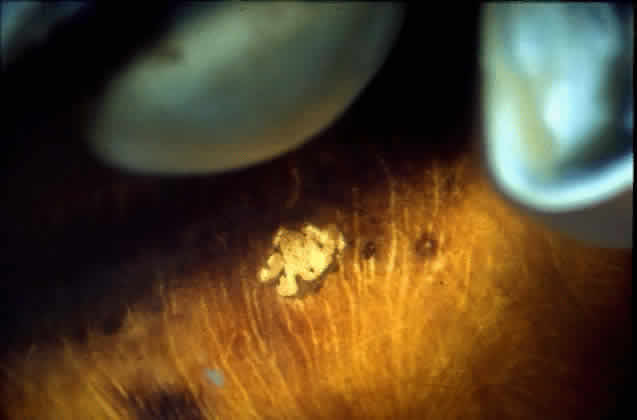

Drusen, ophthalmoscopically visible deposits present between the RPE basement membrane and the inner collagenous layer of Bruch's membrane, are more prevalent with increasing age (Fig. 9). A morphometric study of Bruch's membrane, the choriocapillaris, and the choroid in aging was performed by Ramrattan and associates21 in eyes obtained from patients ranging from 6 to 100 years old with normal maculae. The findings revealed that the thickness of Bruch's membrane in the normal macula increases by 135% between the 1st and 10th decades of life (from 2 to 4.7 μm), while the choriocapillaris density and diameter and the choroidal thickness generally decreased in a linear fashion in the same time interval. Statistical analysis of the morphometric data showed that the thickness of Bruch's membrane was directly related to age alone and that there was no relationship between age-related atrophy of the choriocapillaris and changes in Bruch's membrane thickness.

Fig. 9. Solitary nodular drusen (arrow) resting on inner surface of Bruch's membrane. (H & E, × 63)